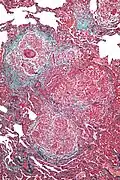

-

High magnification micrograph of hypersensitivity pneumonitis showing granulomatous inflammation. Trichrome stain.